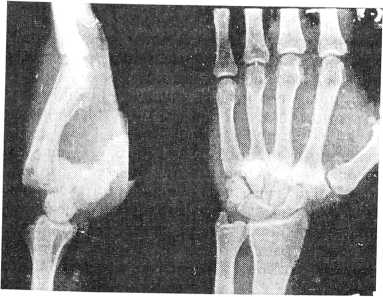

Рис. 1.

Г., 29 лет, обратился в приемное отделение НИЦТ “ВТО” 24.11.96 г. после падения на лестнице и сильного удара с упором на локтевой край правой кистью. При клинико-рентгенологическом обследовании установлен редкий случай изолированного вывиха четырех пястных костей (рис. 1). Под местной анестезией 2% раствором новокаина вывих был вправлен, и наложена ладонная гипсовая лонгета (без разгибания кисти и упора на область головок пястных костей!). На контрольных рентгенограммах после вправления выявлен подвывих 2—3—4—5-й пястных костей (рис. 2). Однако больной от повторного вправления подвывиха и госпитализации отказался. Через неделю из-за усилившихся болей в области кисти лонгета была снята, и рентгенограммы показали полный (повторный!) вывих 2—3—4—5-й пястных костей (рис. 3). Под внутривенной анестезией 2% раствором новокаина вывих пястных костей был вправлен и произведена чрескожная чрескостная фиксация двумя спицами сроком на 6 недель (рис. 4). Осмотрен через год, функция правой кисти полная, жалоб не предъявляет.